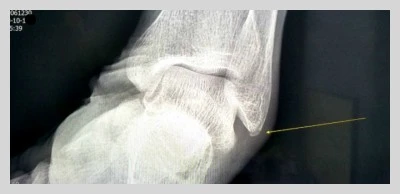

제 경우로 봐도 이점 확실한 데요, 당시 왼발목 뼈에 실금이 가, 한 달 반 동안 불편하게 지냈답니다.

쓰러진 당일에는 뇌혈관 문제인가 싶어 그에 골똘하느라 응급실에서도 발이 아픈 줄을 몰랐어요.

식당에 걸어 들어가서 아무렇지 않게 저녁도 잘 먹고 난 그 이튿날 아침부터 찌릿한 통증으로 왼발을 디딜 수가 없는 거였습니다.

통각점인 복숭아뼈 부분을 엑스레이로 찍어보니 넘어지면서 바닥에 부딪쳐 복숭아뼈에 약한 골절상을 입어 깁스해야 한대서 약식으로 조치를 취했는데요.

부목을 대고 정식 깁스를 하면 보행에 지장이 있을 터라 보호대로 6주째 발을 칭칭 감싼 채 모셨답니다.